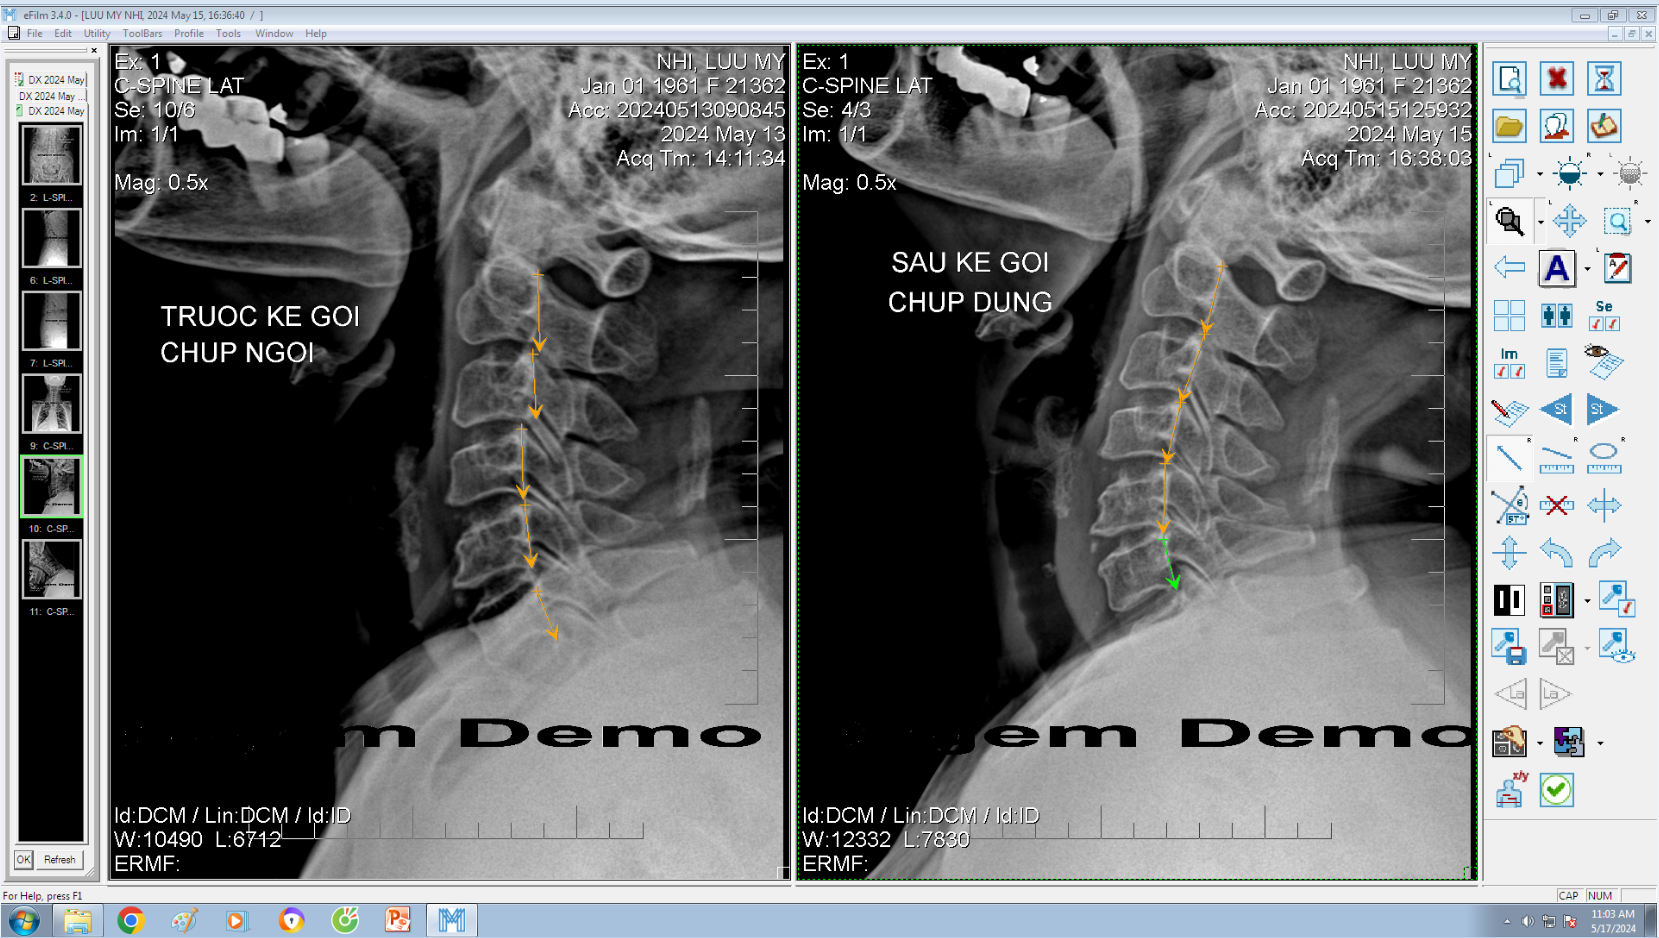

DOCTORLOAN đã thành công trong điều chỉnh xương khớp về đúng vị trí trong thời gian ngắn